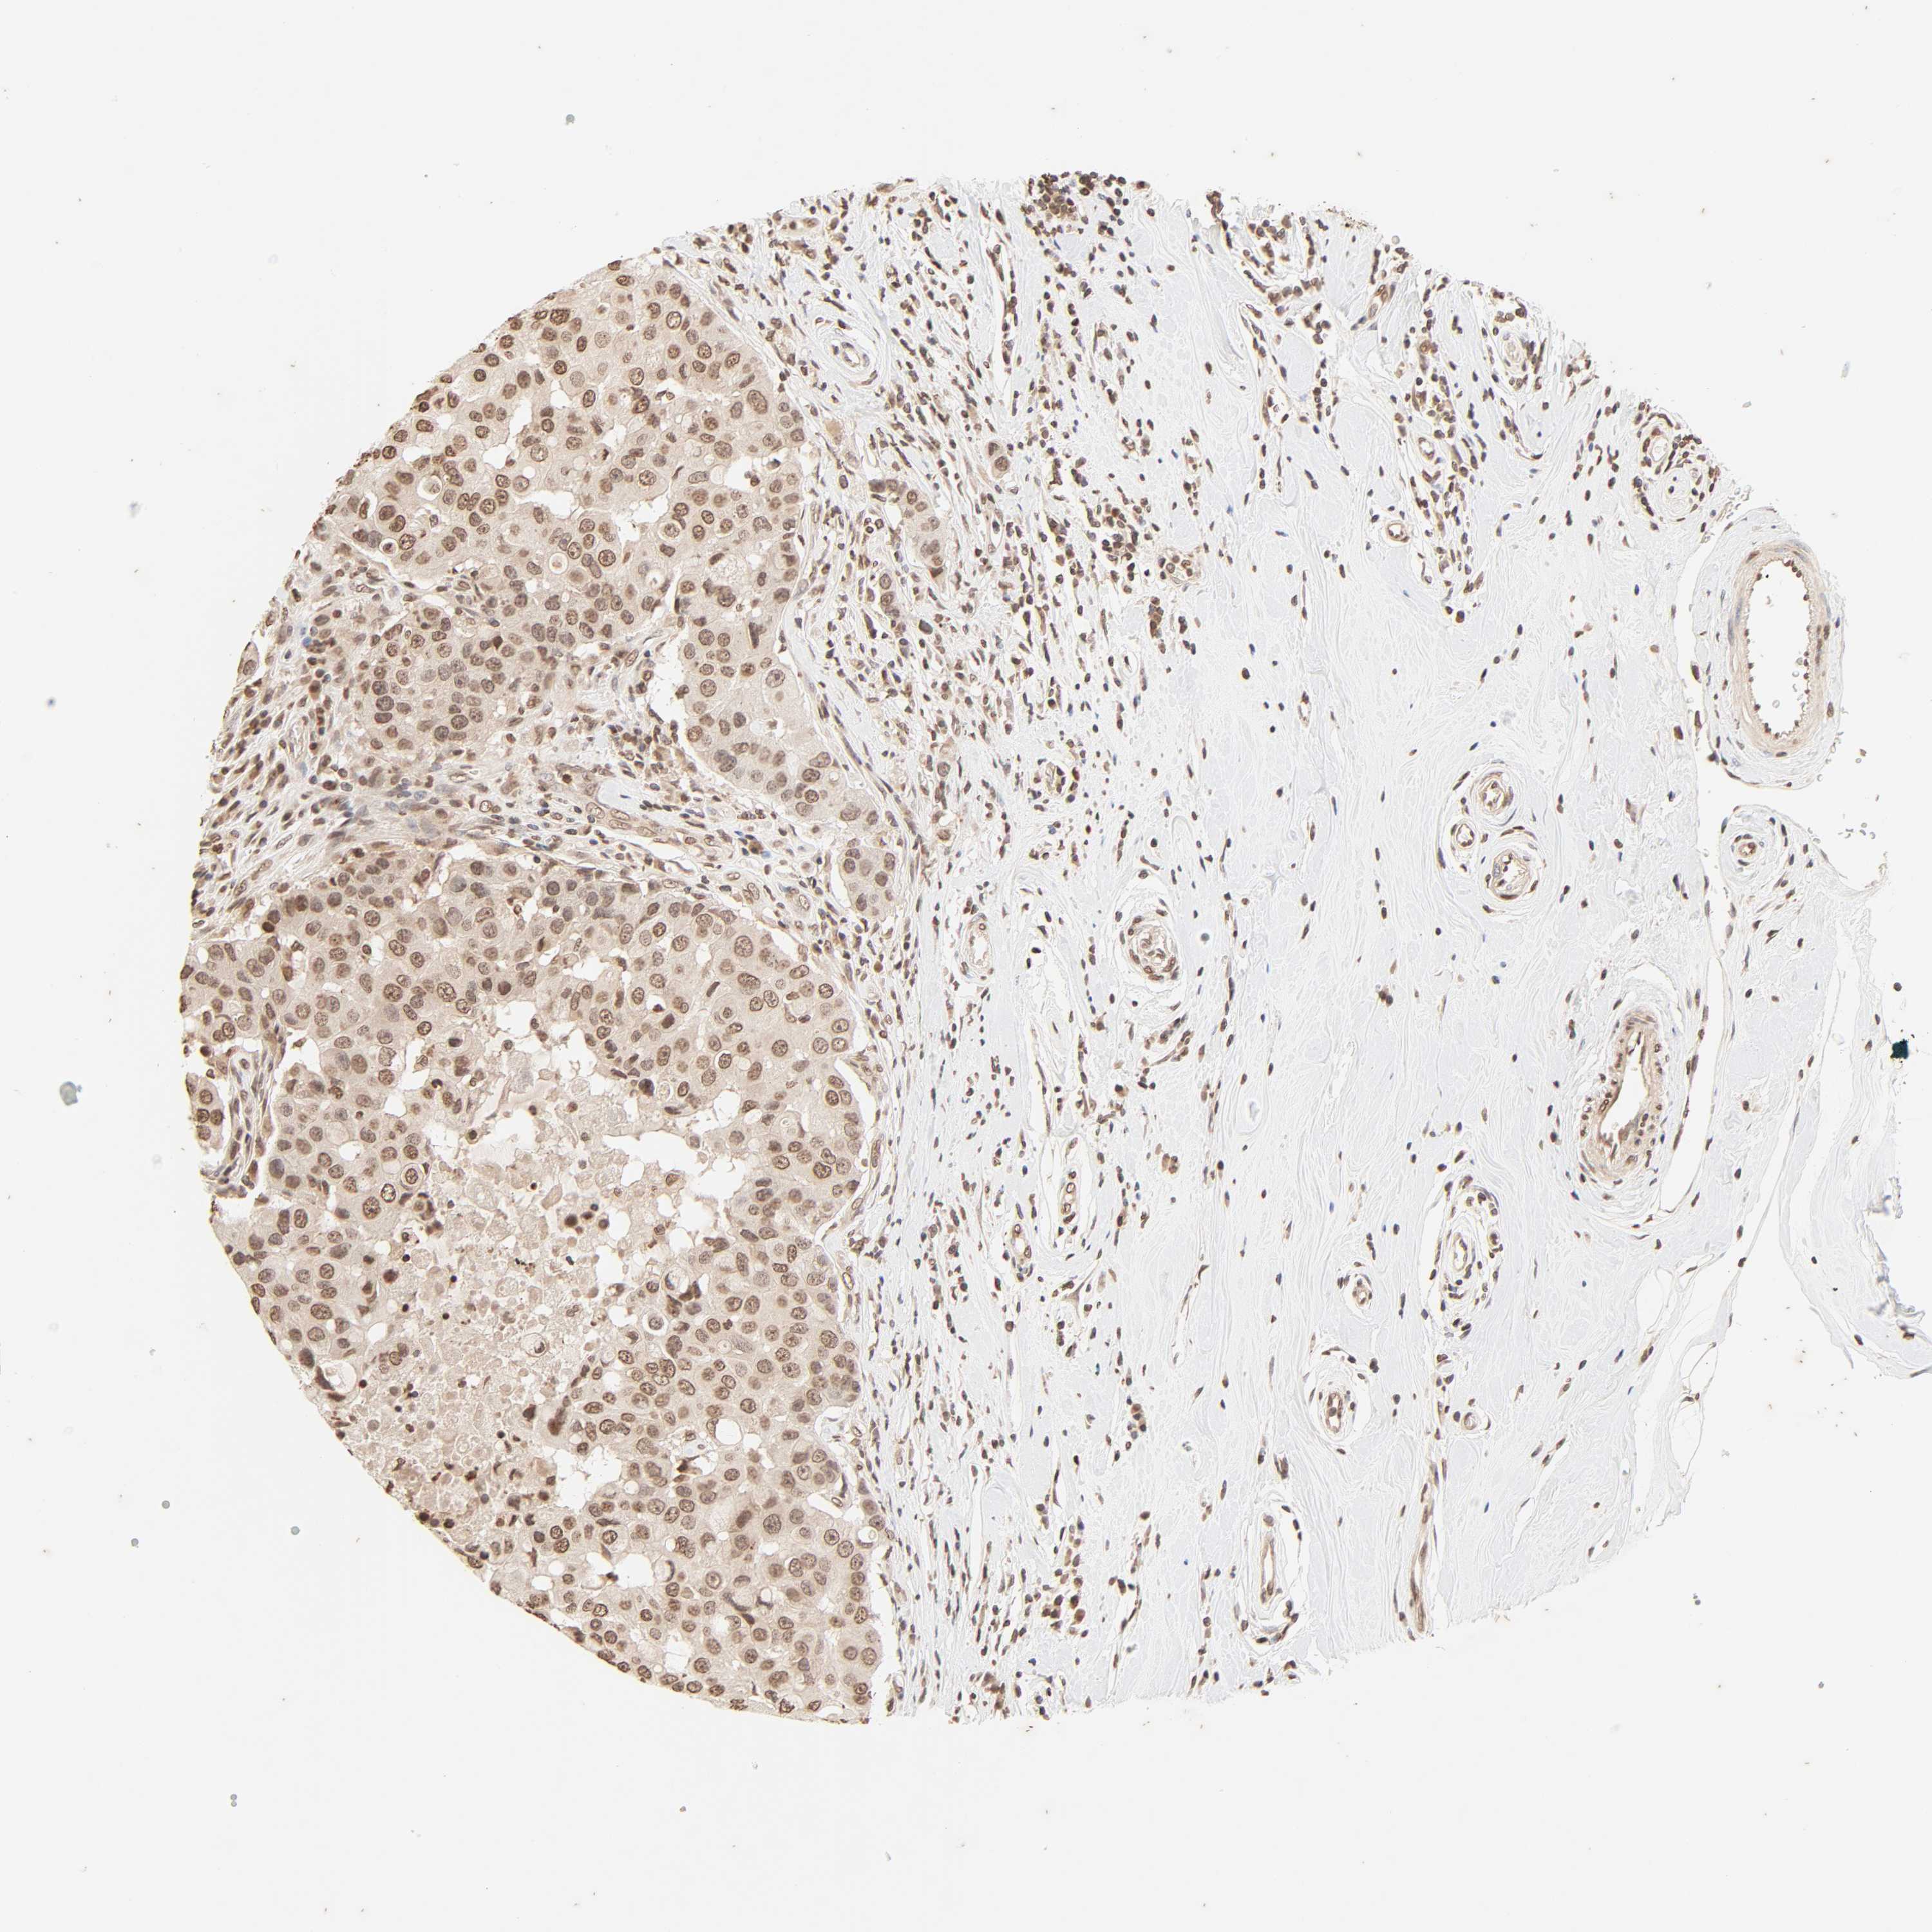

CANCER BREAST CANCER Show tissue menu

BRCA TCGA BRCA VALIDATION PROTEIN EXPRESSION

ANTIBODIES

AND

VALIDATION